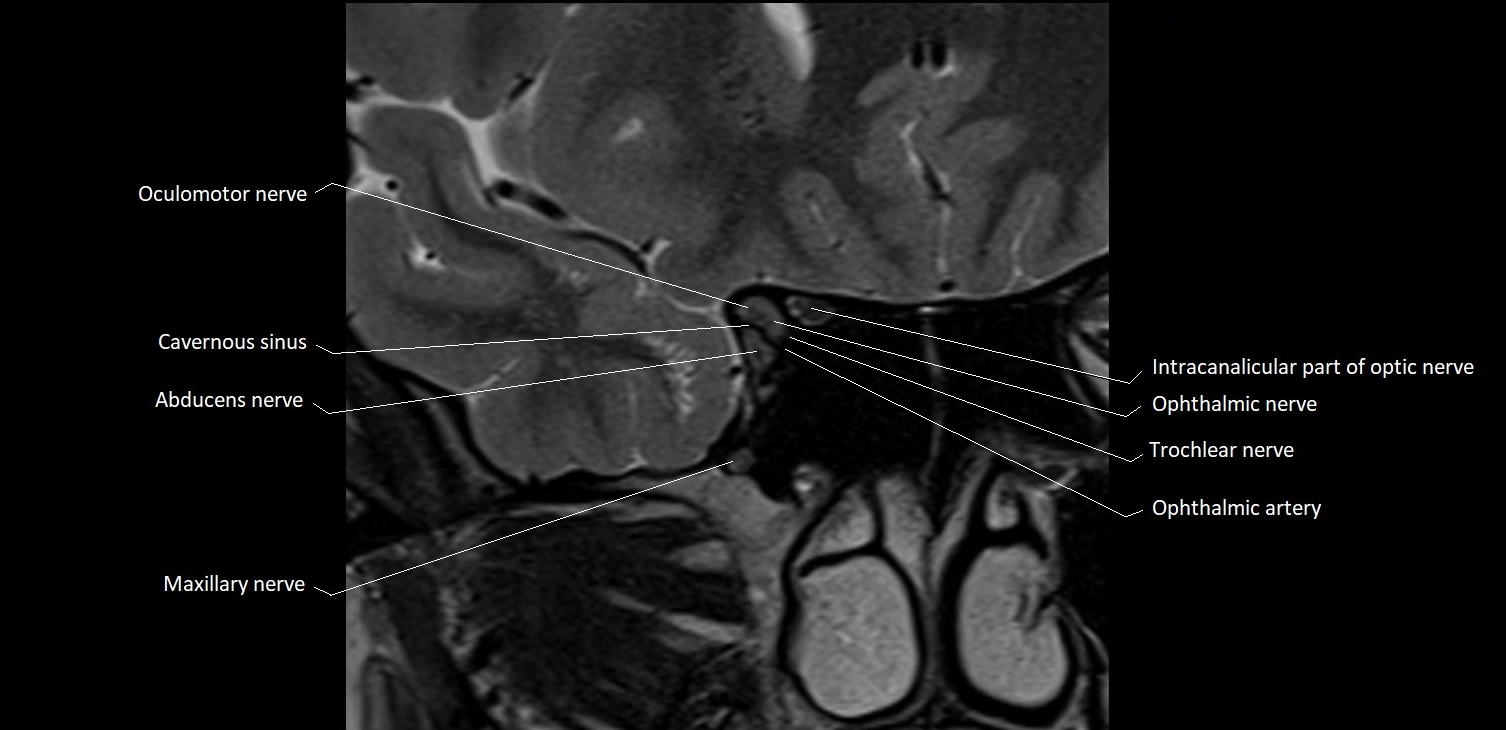

- Abducens nerve (Cranial nerve VI)

- Trochlear nerve (Cranial nerve IV)

- Oculomotor Nerve (Cranial Nerve III)

- Maxillary nerve

- Intracanalicular part of optic nerve

- Trigeminal ganglion